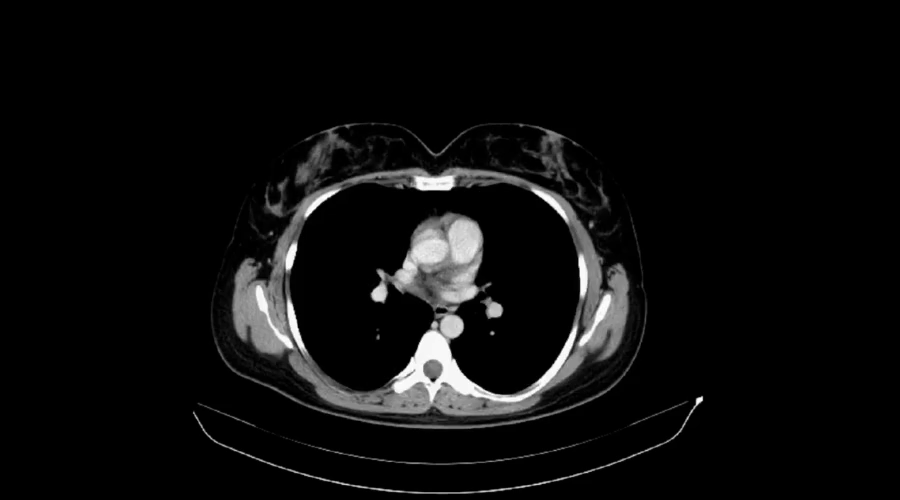

CT:看得更清晰的“分层扫描”

CT的学名是“计算机断层扫描”。

🖥️简单说,就是让人躺进一个“大圆环”里,用X射线对人体进行一层一层的扫描,再由电脑合成横断面图像,就像把一根黄瓜切成薄片,每一片都能看清。

它比DR强在哪?

🔍能区分非常接近的器官和组织(比如大脑中的灰质和白质)

🔍非常适合看出血、肿瘤、血管病变(如脑出血、肺结节、主动脉夹层)

🔍可进行三维重建,立体观察复杂结构(如颌面骨骼)

优点:分辨率高、扫描快、对急诊尤其重要

· 辐射剂量高于DR,但一次常规体检CT的辐射在安全范围内。

· 如需做“增强CT”(注射造影剂),需提前告知医生有无碘过敏史、肾功能是否正常、是否患有甲亢等。

· 检查时需配合指令短暂屏气,身体保持不动,以获得清晰图像。